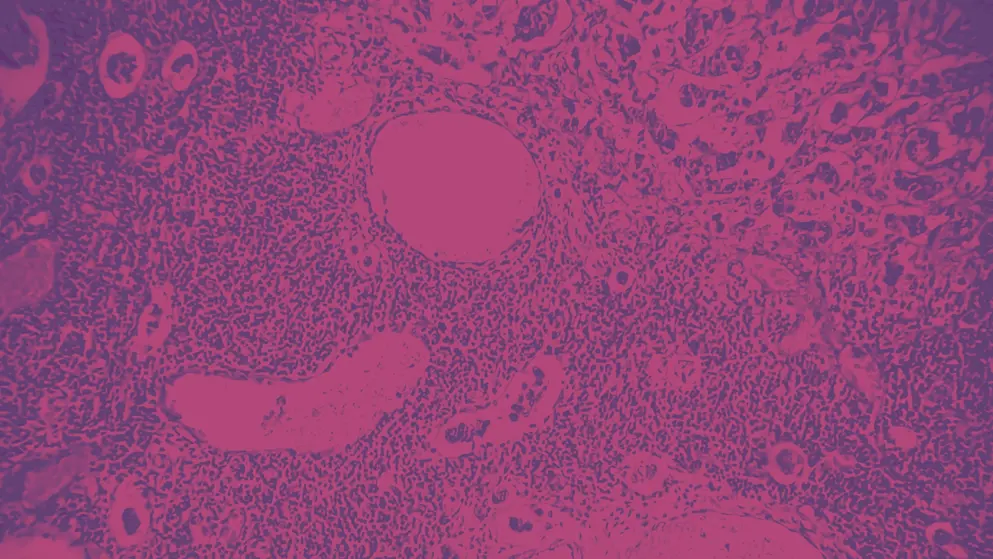

Phase III trial updates and a HER2-low debate